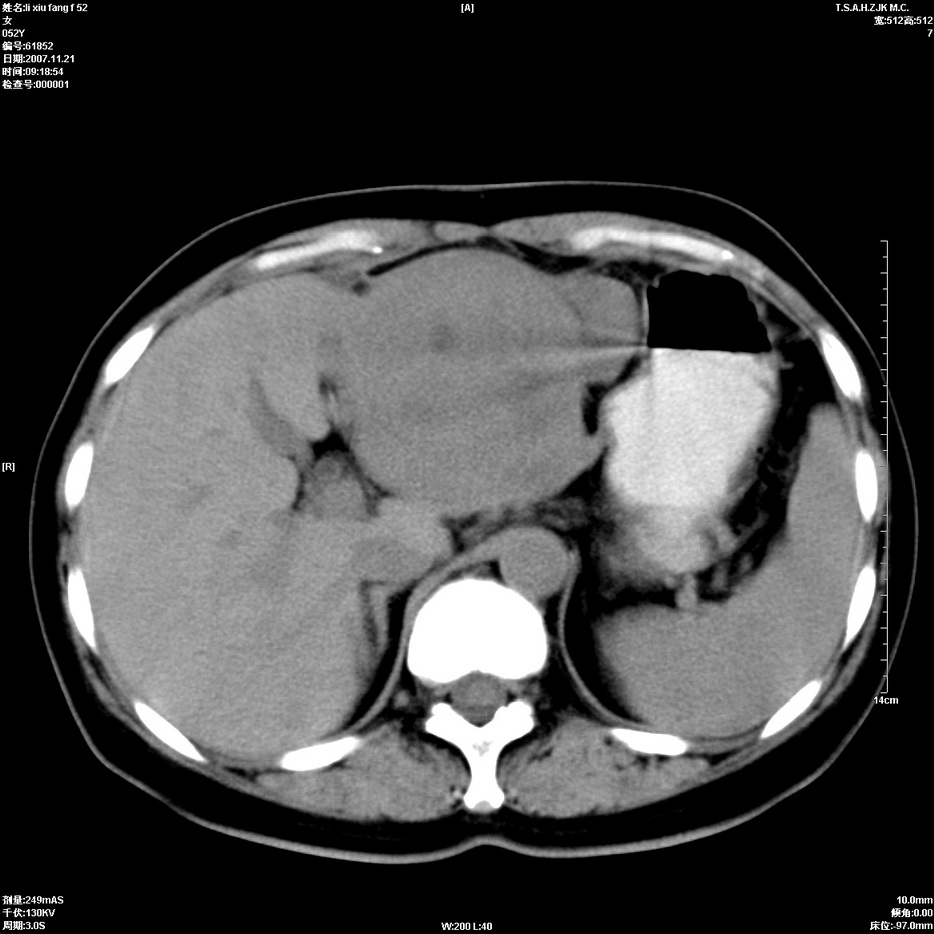

标题: CT12858:女,52岁,胎甲球蛋白861肝左叶占位,肝癌。下腔静 [打印本页]

标题: CT12858:女,52岁,胎甲球蛋白861肝左叶占位,肝癌。下腔静

肝左叶巨大低密度灶肿块,增强符合快进快出表现,有动静脉交通支;静脉期,下腔静脉内有充盈缺损,afp明显升高,支持肝癌并下腔静脉癌栓形成。

支持楼主   门静脉主干及左支癌栓形成

以下是引用拾荒者在2008-4-15 22:57:00的发言:[br]肝左叶巨大低密度灶肿块,增强符合快进快出表现,有动静脉交通支;静脉期,下腔静脉内有充盈缺损,afp明显升高,支持肝癌并下腔静脉癌栓形成。